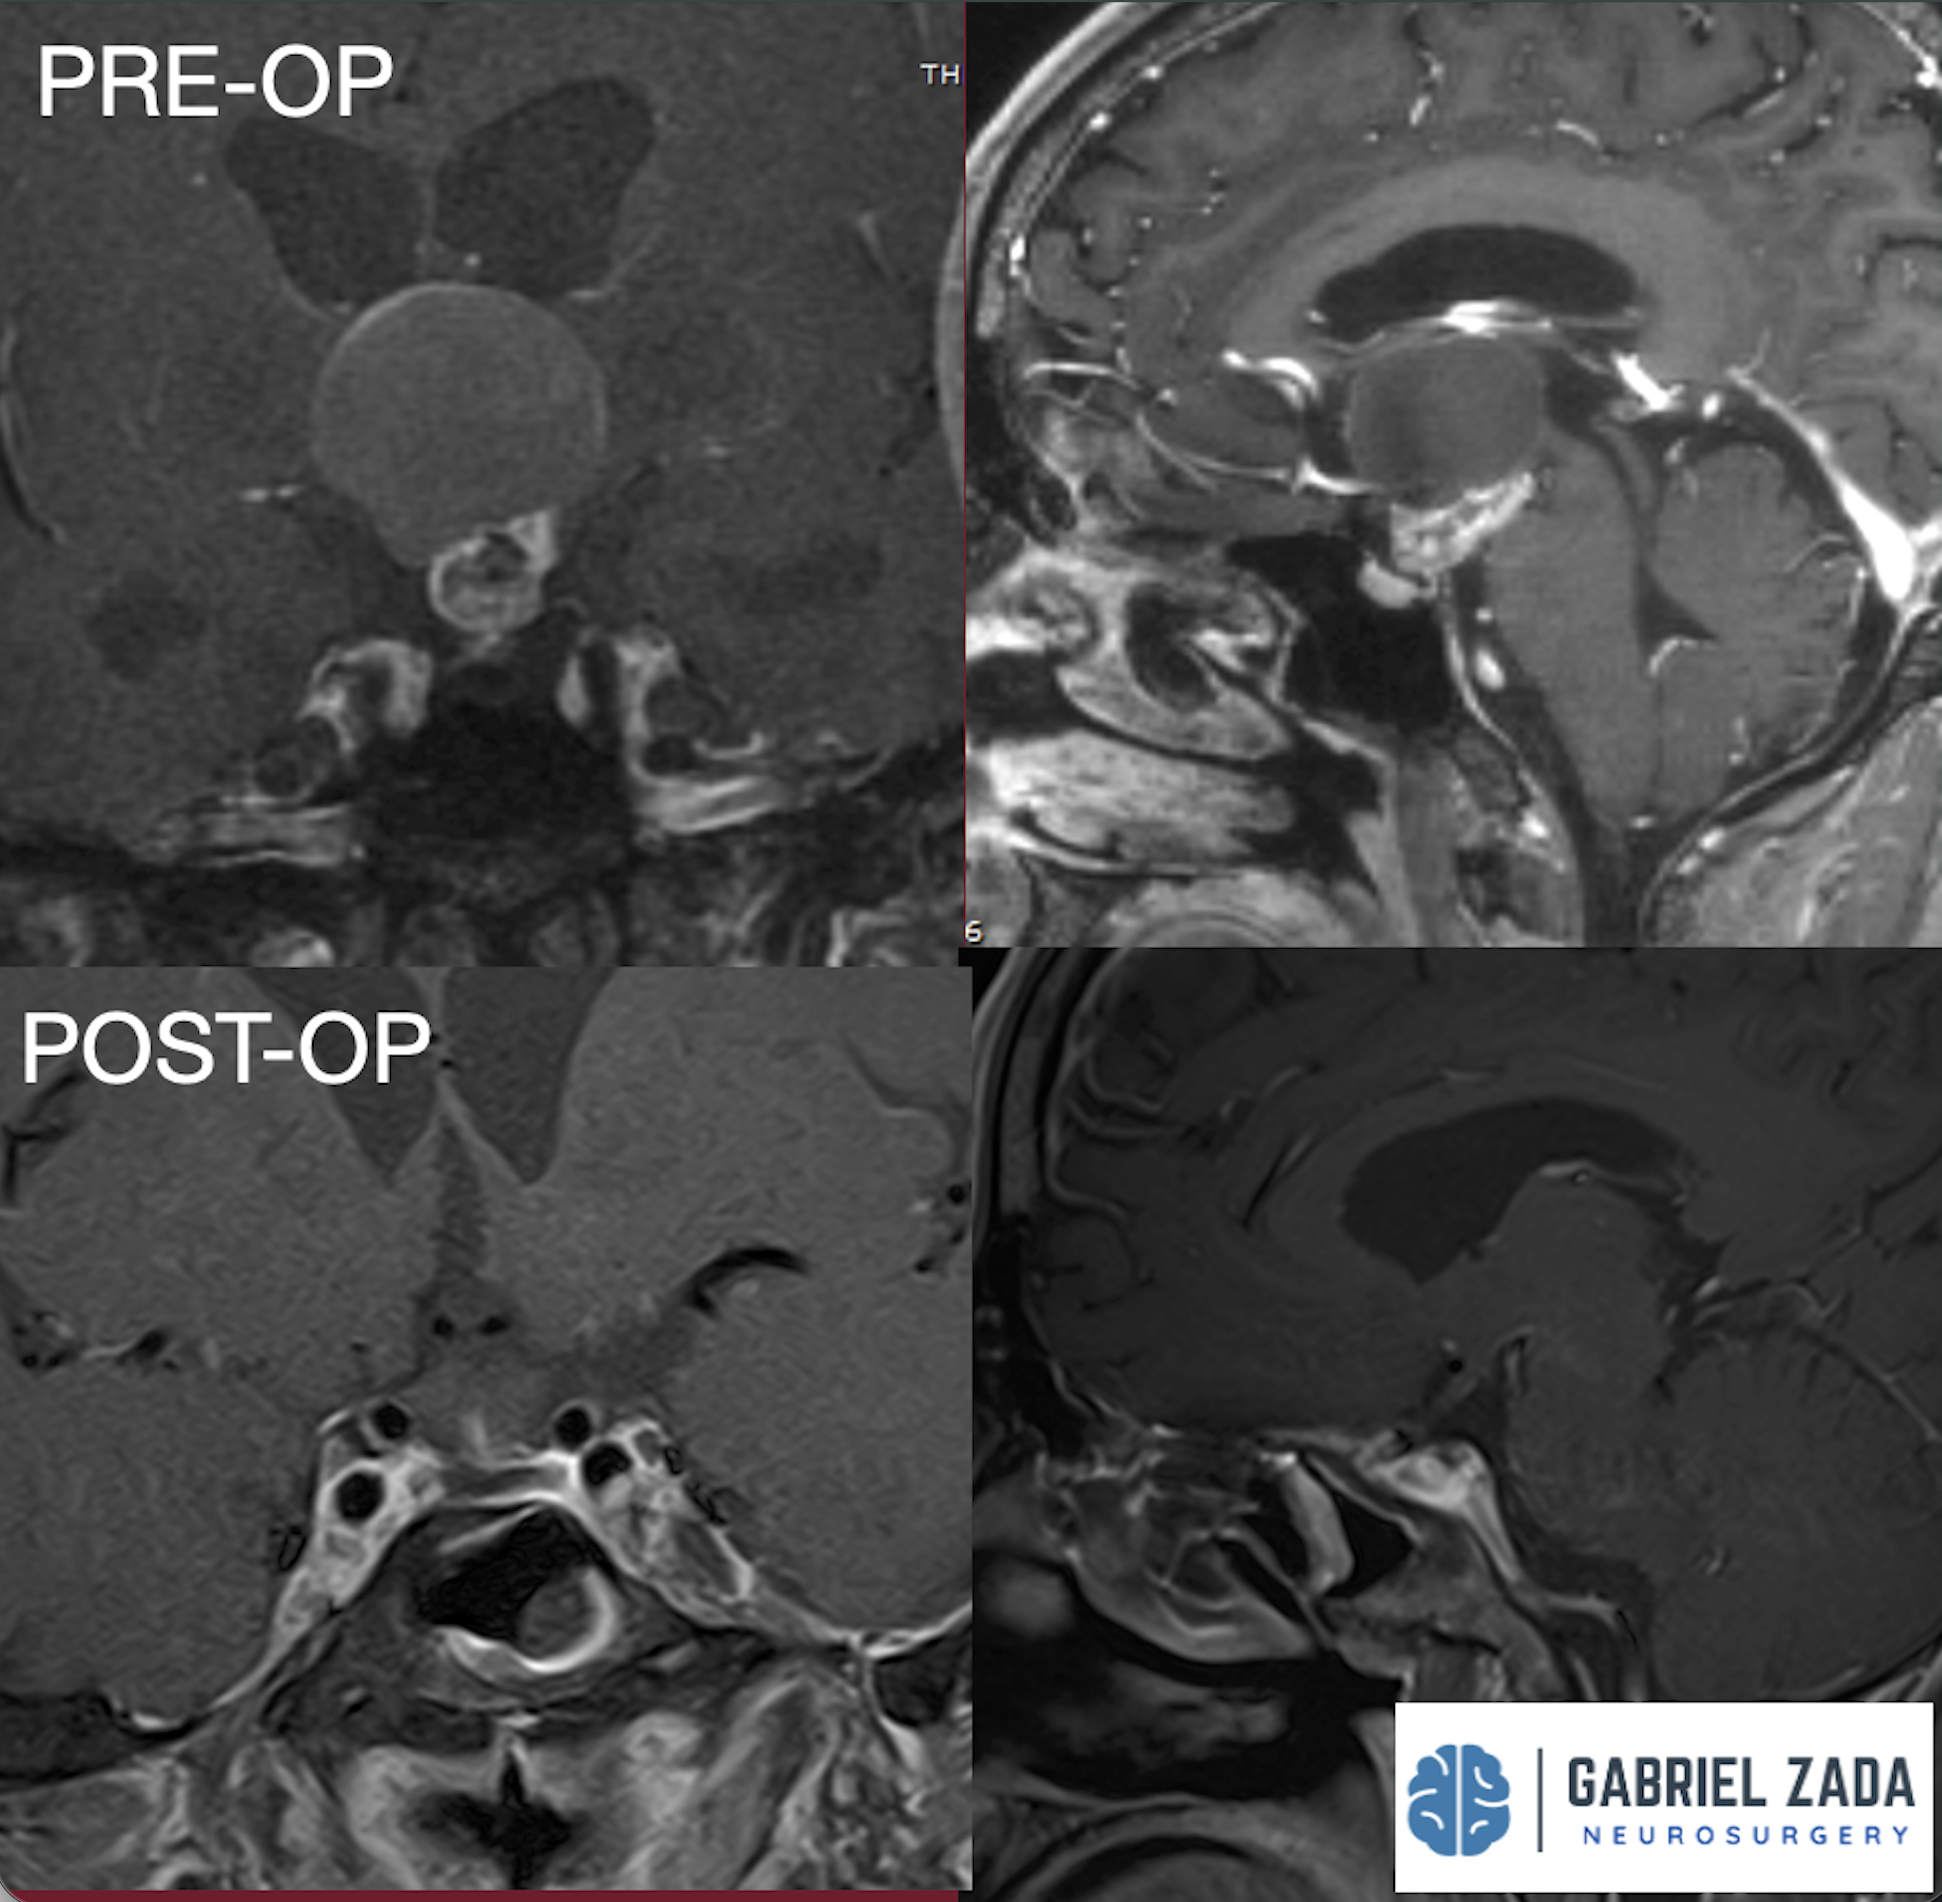

Explore this comprehensive gallery featuring pre‑ and post‑operative imaging of patients with skull‑base tumors treated by Gabriel Zada, MD, MS, FAANS, FACS. These cases highlight Dr. Zada’s expertise in advanced neurosurgical techniques and outcomes.

*Representative cases shown for educational purposes. All images de-identified. Individual results vary.